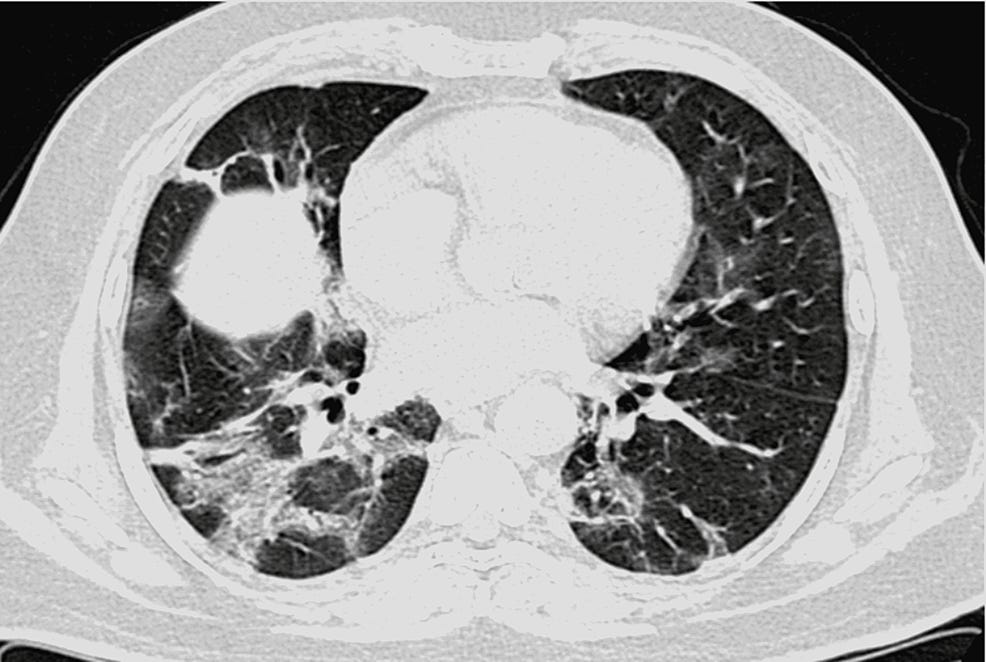

Something clicked for me reading Ricky’s Substack article “30 Clues That Let Us Know COVID Was A Planned Operation | Part VIII: EVALI” and I can’t stop thinking about it. He points out that the lung injury labeled as “COVID lung” looked almost identical to what doctors were already seeing in heavy vape users for years. Ground glass imaging. Scarred bronchioles. Oxygen exchange that never quite recovers. The clinical picture of bronchiolitis obliterans, more commonly called popcorn lung. The common factor is not some mythical viral enemy. The common factor is heat… plus nanoparticles.

Radiologists call the result “COVID lung” or “popcorn lung”. The mechanism has been staring us in the face for years. It’s. So. Simple. Call it what you want. Popcorn lung. Hair product lung. COVID lung. Nanoparticle lung. Not a virus making my long not work lung.